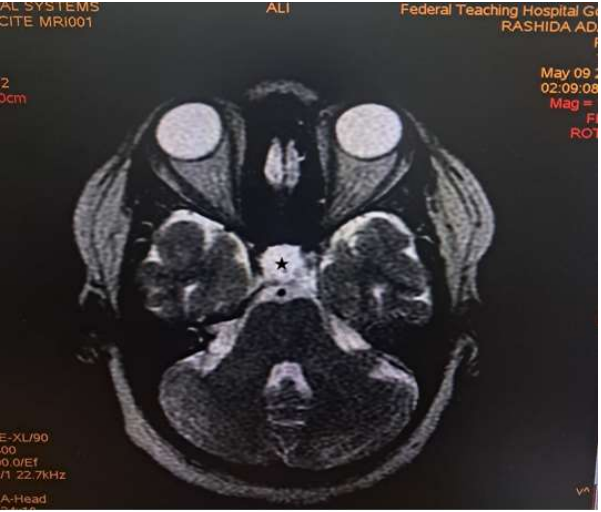

Magnetic Resonance Imaging (MRI) revealed expansion of the sella with a well-defined fairly rounded lesion measuring 15 X 14 X 15mm (width X AP X H). It is hypointense on T1W, hyperintense on T2W and suppressed on FLAIR sequence. Rim enhancement is seen post contrast. The mass is inseparable from the optic chiasma suggestive of compression.

Figure 2: Axial T2W image of the brain showing a hyperintense rounded intrasellar mass lesion (black asterisk).

Rathke’s cyst is visualised on magnetic resonance imaging as a lesion located in the intermediate lobe of the pituitary. Its largest diameter usually does not exceed 20 mm9. The cyst may have varying intensity against the cerebrospinal fluid, although it is more often hypointense in T1-weighted images and hyperintense in T2-weighted images. RCC image captured on MRI is described as “an egg in a shell [9]. The enhancement of the cyst wall following contrast administration suggests inflammation or metaplasia [11].

Due to its high soft tissue resolution, Magnetic Resonance Imaging (MRI) is the primary diagnostic technique for RCC9. It also determines the cystic content and fluidity of the cyst which is useful in planning for subsequent patient’s management10. Fifty percent are hyperintense on T1W (due to high protein content) while 50% are hypointense. On T2W, 70% are hyperintense, 30% iso or hypointense and 20% have hypointense rim. T1W Post contrast images usually show no enhancement. However, a thin enhancing rim may be seen when cyst wall infection is present [19-20]. The case presented revealed expansion of the sella with a well-defined fairly rounded lesion measuring 15 X 14 X 15mm (width X AP X H). It is hypointense on T1W, hyperintense on T2W and suppressed on FLAIR sequence. Rim enhancement is seen post contrast. The mass is inseparable from the optic chiasma suggestive of compression. The appearance of the cyst confirmed no haemorrhage or debris within the cyst. However, the rim enhancement suggest inflammation of the cyst as explained in the text. The finding of optic chiasma compression may explain the visual impairment and the bitemporal hemianopia seen in the patient.